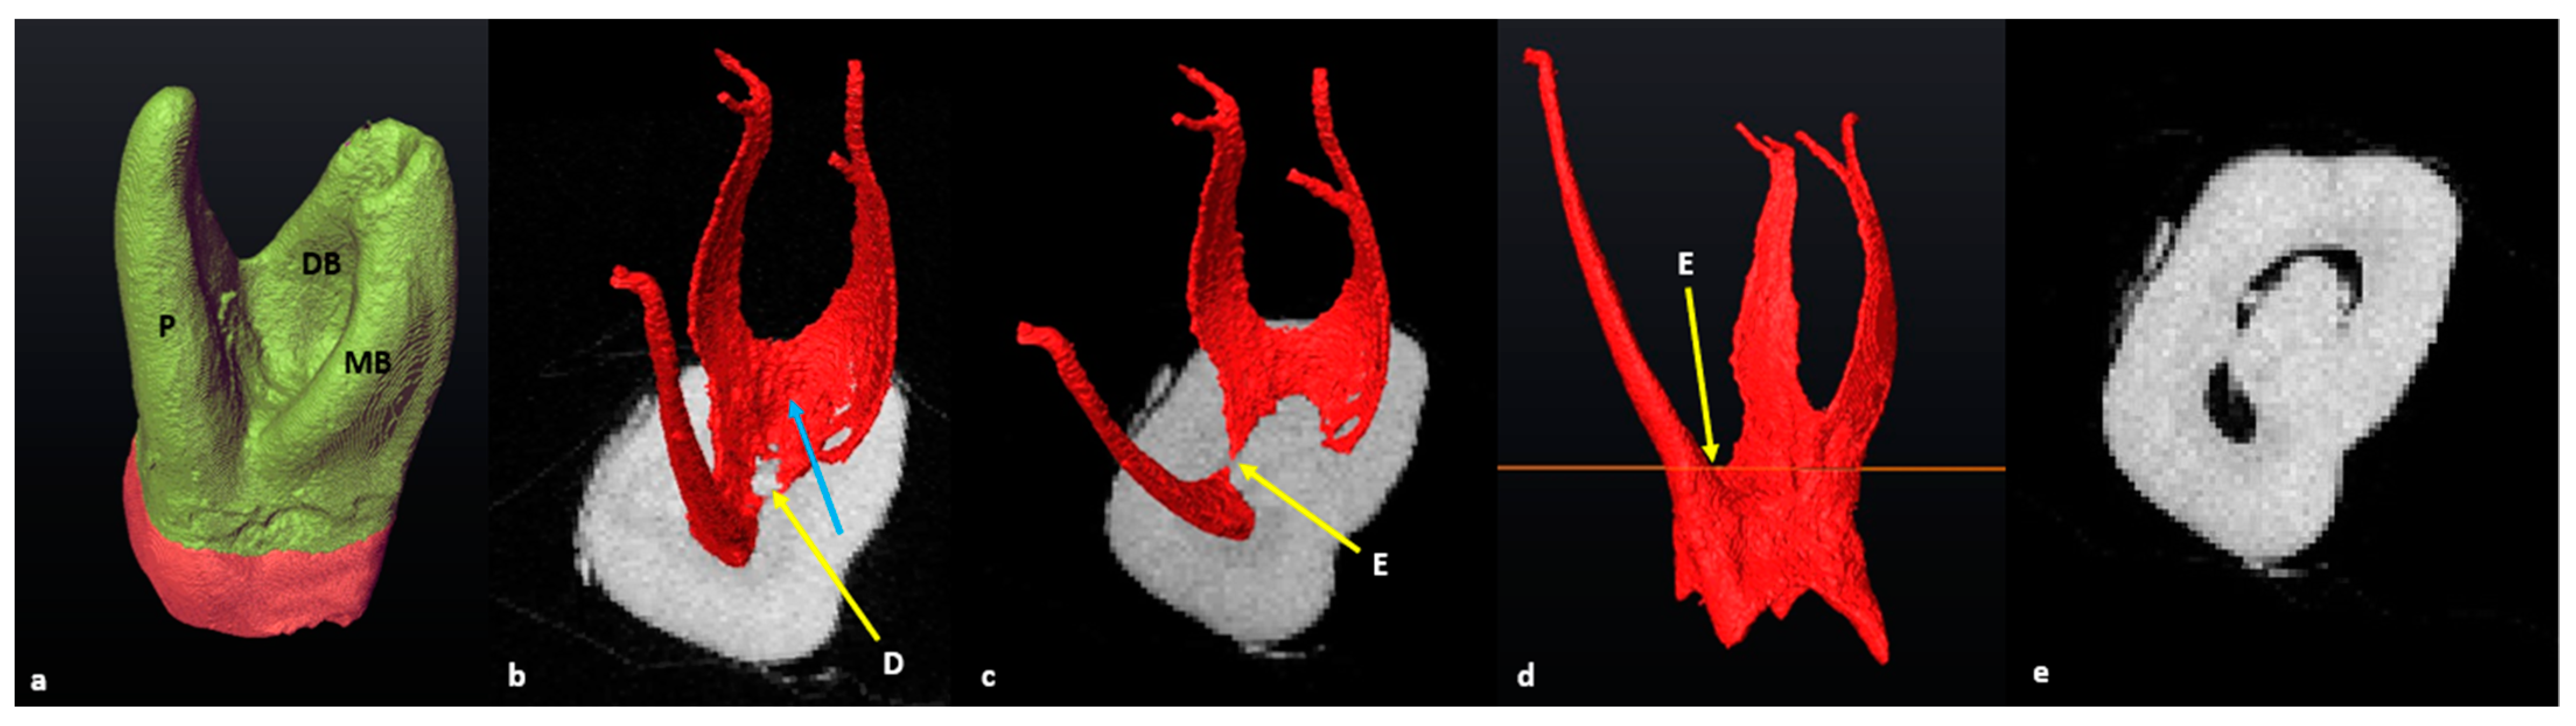

3.2. Mandibular First Molars: Three Rooted